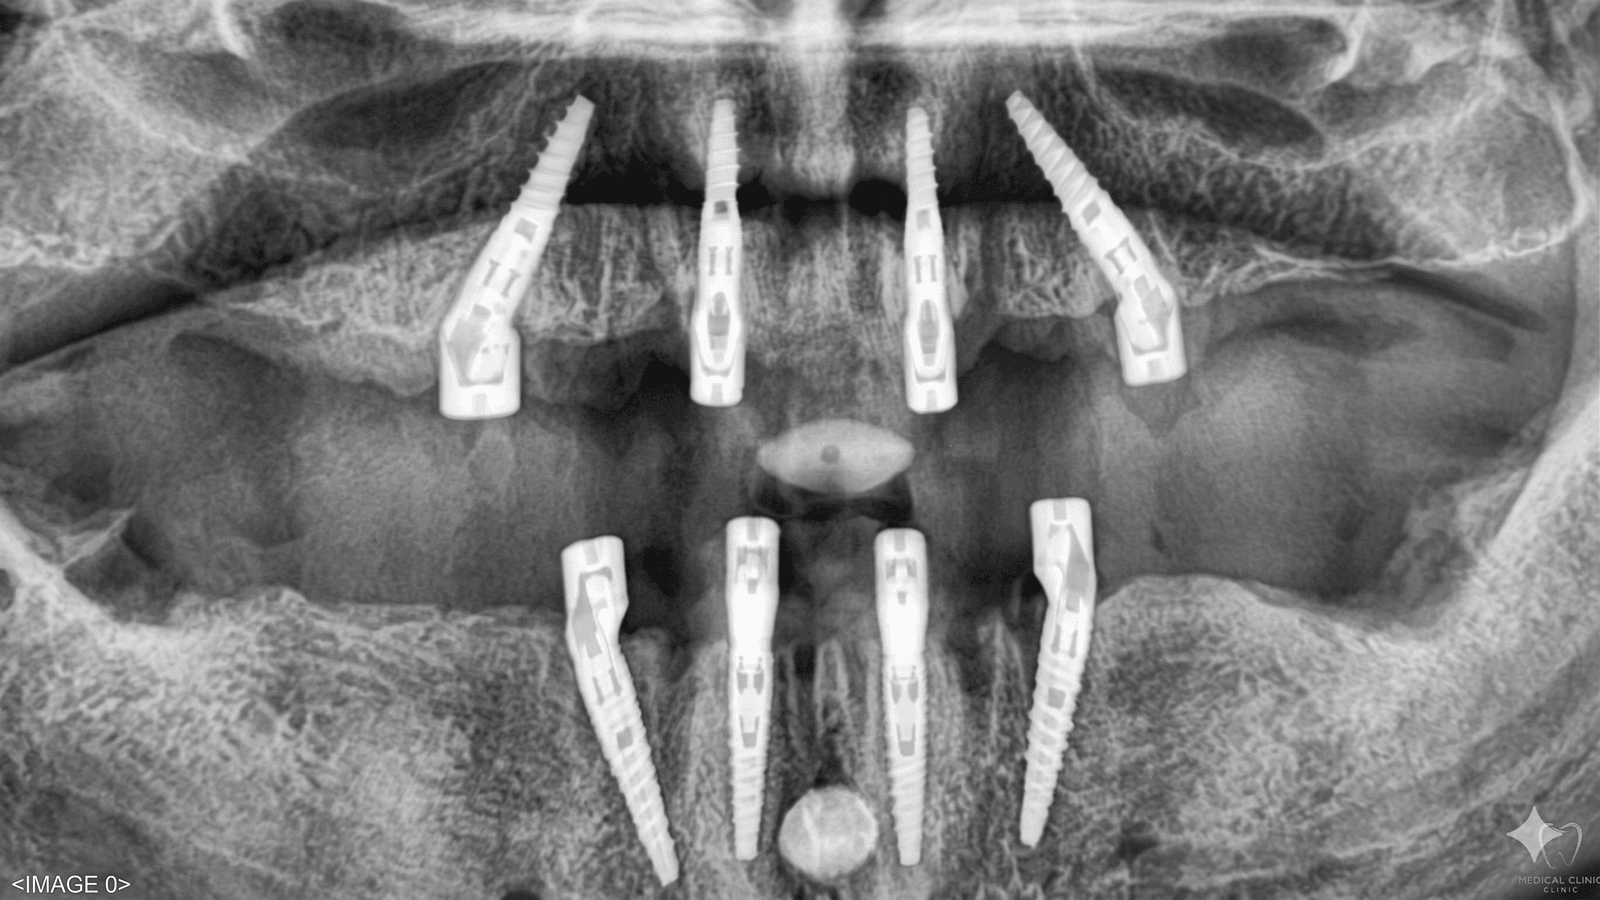

Inviaci una panoramica dentale, qualche foto del problema o anche solo una descrizione di quello che senti. Puoi scriverci dal modulo, su WhatsApp, via email, o chattare direttamente con Emma, la nostra assistente AI disponibile 24/7.

Arrivi a Tirana e ti accogliamo direttamente in aeroporto. Visita preliminare, conferma del piano, poi si procede. I dentisti parlano italiano, le cliniche sono moderne, sterili e attrezzate con CBCT 3D, scanner intraorali e tecnologia CAD/CAM.

Materiali certificati CE, protocolli europei, sale chirurgiche dotate di tutto il necessario per impianti, faccette, riabilitazioni complete e chirurgia avanzata.